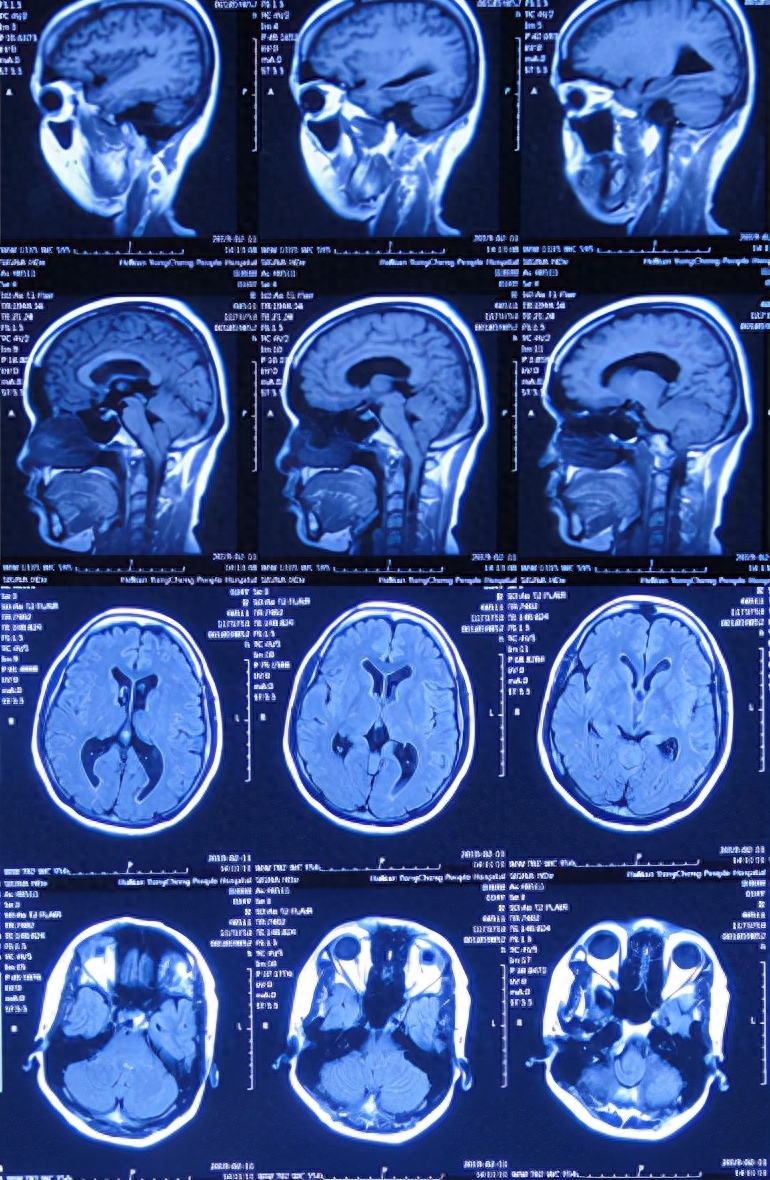

图-2:2019年2月12日头颅核磁

图-3:2019年2月13日头颅核磁

小脑扁桃体下疝减压术后20天即2019年3月6日,查头颅、颈椎核磁发现仍有脊髓空洞(图-8、图-9)。

图-8:2019年3月6日头颅核磁

图-9:2019年3月6日头颅核磁